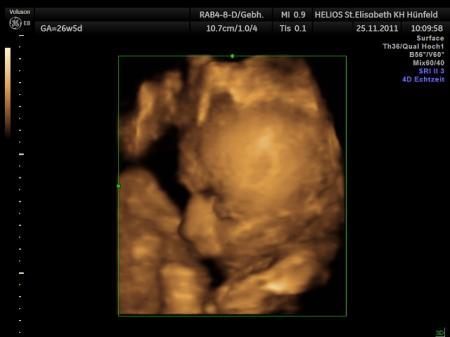

Bild zu

Süßes Bild Bodenklappe LG Anja